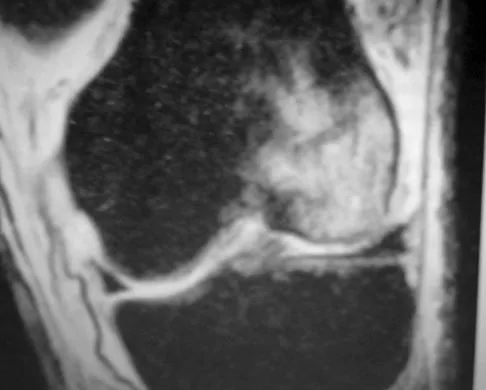

The MRI findings shown in Figure 51 would most likely create which of the following signs and symptoms?

Explanation